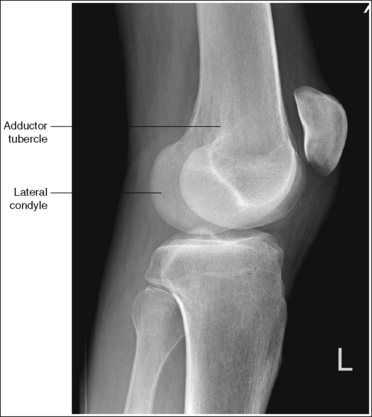

• Distinguishing lateral and medial condyles. The first step you should take when evaluating an image on which the distal condylar surfaces are not aligned is to determine which condyle is the lateral and which is the medial. The most reliable method for identifying the medial condyle is to locate the rounded bony tubercle known as the adductor tubercle. It is located posteriorly on the medial aspect of the femur, just superior to the medial condyle. The size and shape of the tubercle are not identical on every patient, although this surface is considerably different from the same surface on the lateral condyle, which is smooth. Once the adductor tubercle is located, the medial condyle is also identified. Another difference between the medial and lateral condyles is evident on their distal articulating surfaces. The distal surface of the medial condyle is convex, and the distal surface of the lateral condyle is flat.